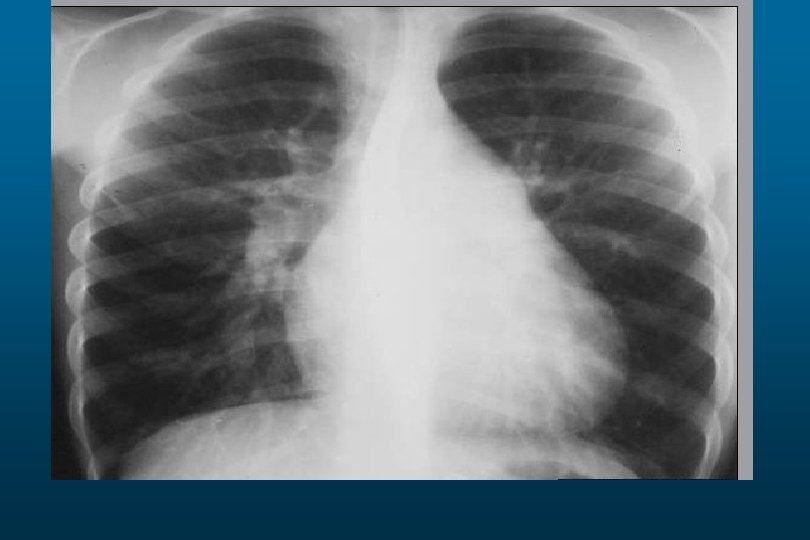

Pleural Effusion